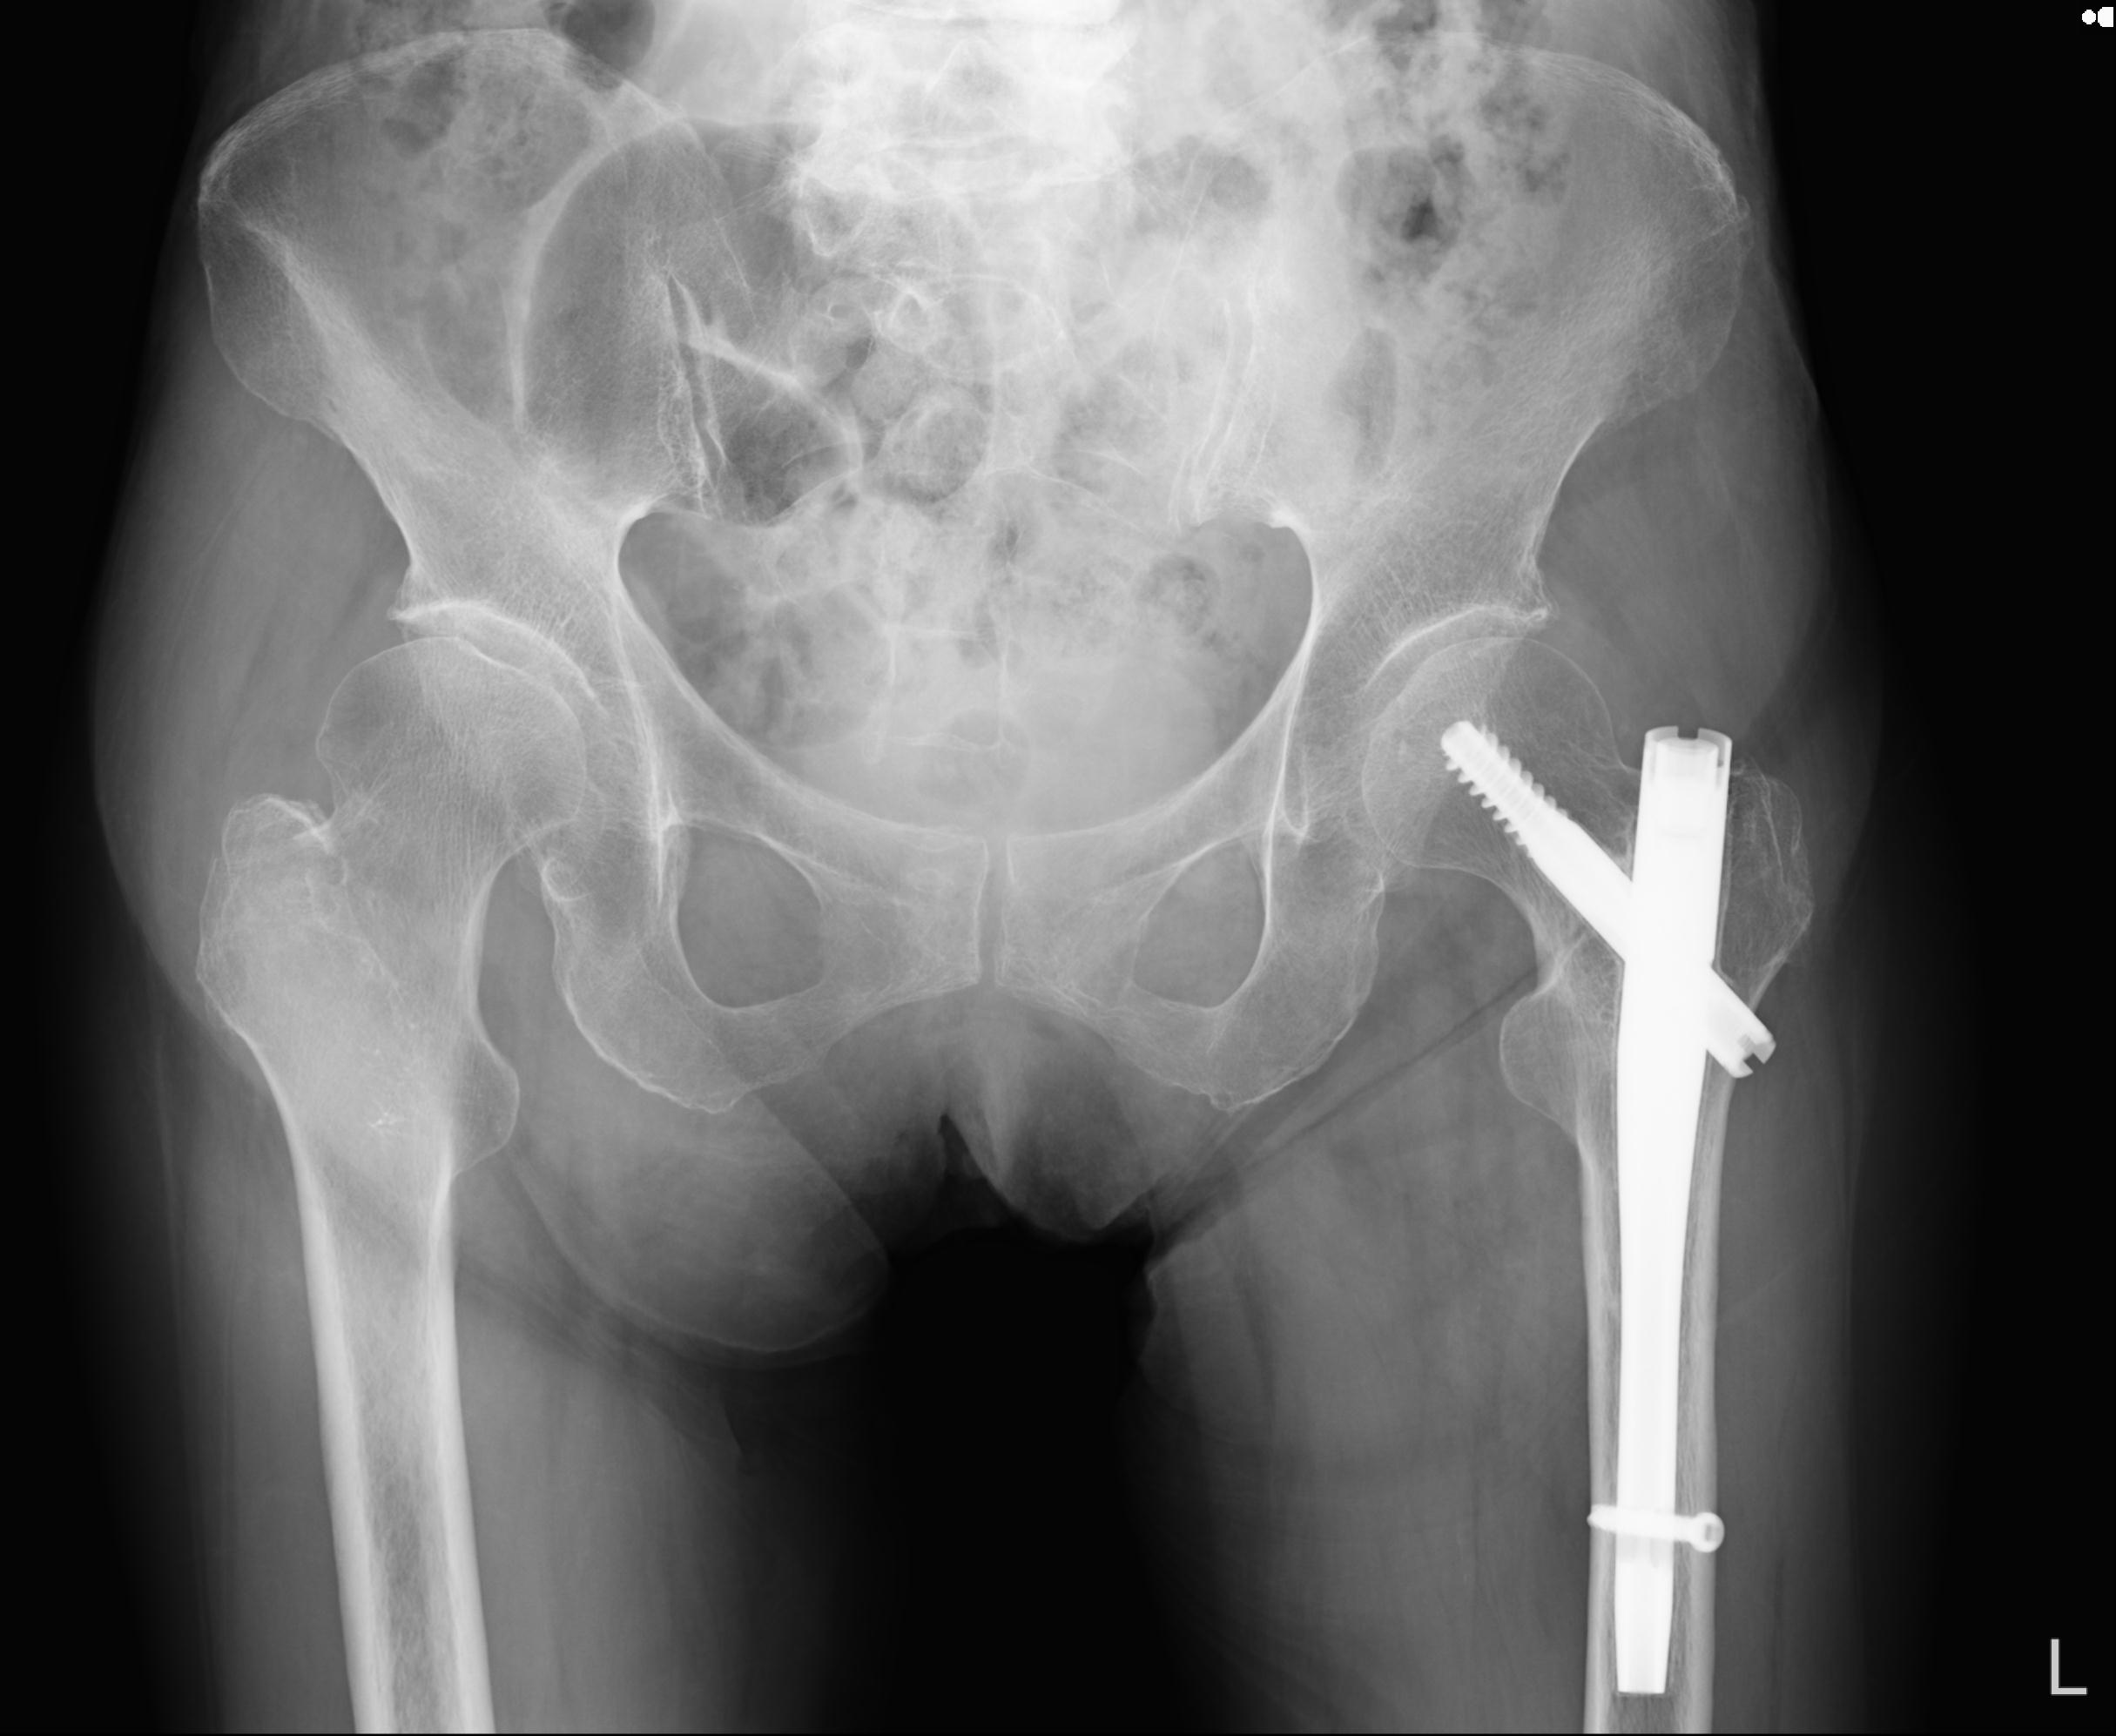

46666 1/28 両股正面+軸と 1/26 右手関節 2R 76歳女性 右転子部骨折

37 1/18 両股正面+軸 1/22 2R 86歳女性 右転子下

102811 1/13 股関節 2R 1/19 2R 80歳女性 右DHS